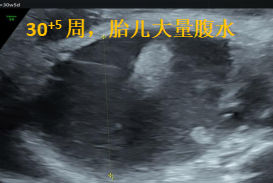

37歲的M女士,這是她的第三個寶寶,從懷孕到30周,一路平順走來。直到孕30+3周時,在當地做胎兒超聲提示“胎兒腹盆腔大量積液”,這個陌生的醫學術語曾讓全家徹夜難眠。

次日,她們來到了昆明安琪兒婦產醫院產前診斷中心謝敏醫生的門診,在與超聲科吳云萍醫生的共同評估下,發現寶寶腹腔內大量積液,腸管受壓攣縮,但經過詳細地畸形排查,并沒有發現其他的結構異常或生長發育方面的問題。通過充分的遺傳咨詢和分析,M女士一家決定竭盡全力救治與她已經共度了200多天的寶寶。